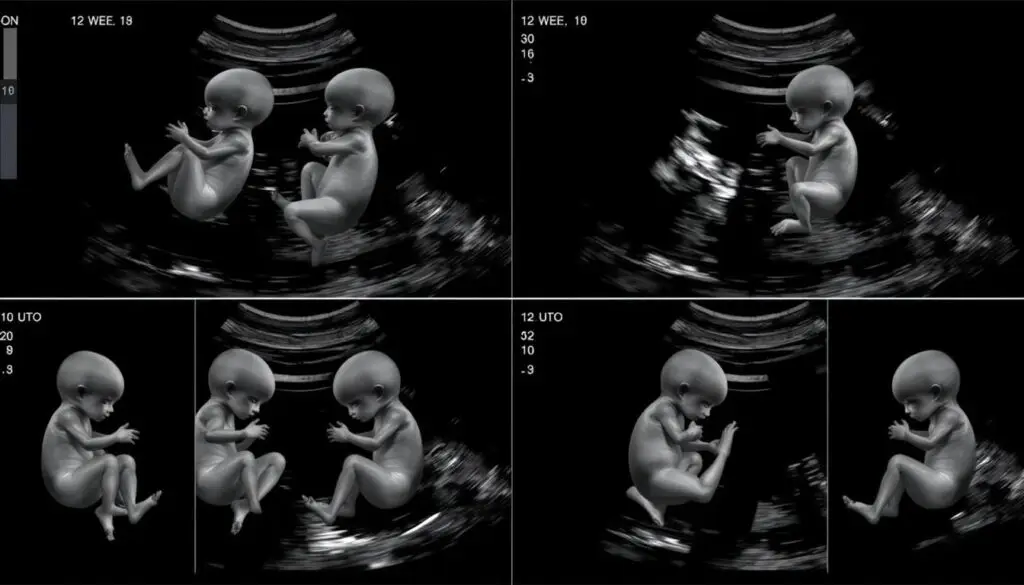

Sekwencja ruchów płodu w 12 tygodniu ciąży widoczna podczas badania USG

W 12 tygodniu ciąży Twoje dziecko jest już bardzo aktywne, choć jeszcze nie możesz odczuwać jego ruchów. Podczas badania USG można zaobserwować, jak płód porusza rączkami i nóżkami, obraca się, a nawet ssie kciuk. Te spontaniczne ruchy są niezwykle ważne dla prawidłowego rozwoju układu mięśniowego i nerwowego [16].

Aktywność ruchowa płodu w tym okresie ciąży jest dobrym wskaźnikiem jego zdrowia. Dziecko reaguje na bodźce zewnętrzne, takie jak ucisk brzucha matki, zmieniając swoją pozycję. Rozwija się również odruch ssania i połykania – płód regularnie połyka płyn owodniowy, co stanowi trening dla układu pokarmowego [17].

Pytanie, które często nurtuje przyszłych rodziców, dotyczy ruchliwości płodu z zespołem Downa. Badania naukowe wskazują, że w 12 tygodniu ciąży nie ma jednoznacznych różnic w aktywności ruchowej między płodami z prawidłowym kariotypem a płodami z trisomią 21 (zespołem Downa). Różnice w zachowaniu ruchowym mogą być bardziej widoczne w późniejszych etapach ciąży, ale nie stanowią one diagnostycznego kryterium [18].

Rozwój układu nerwowego płodu umożliwiający pierwsze ruchy

Warto podkreślić, że diagnostyka zespołu Downa i innych aberracji chromosomowych opiera się na kompleksowej ocenie wielu parametrów, takich jak przezierność karkowa, obecność kości nosowej, przepływ w przewodzie żylnym oraz badania biochemiczne krwi matki. Sam wzorzec ruchów płodu nie jest wystarczającym kryterium diagnostycznym [19].

Pierwsze ruchy dziecka, które będziesz mogła odczuwać, pojawią się znacznie później – zwykle między 16. a 20. tygodniem ciąży u kobiet będących w pierwszej ciąży, a nieco wcześniej u kobiet, które już rodziły. Te pierwsze odczuwalne ruchy opisywane są często jako delikatne trzepotanie, przypominające ruch skrzydeł motyla [20].